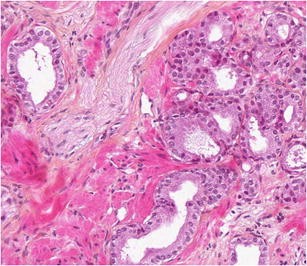

Low-risk prostate adenocarcinoma is classically managed either with active surveillance or radical therapy (such as external radiotherapy or radical prostatectomy), but both have significant side effects. Vascular-targeted photodynamic therapy (VTP) is a focal therapy proposed as an alternative approach for localized, low-volume, and low-Gleason score (≤6) carcinomas. We report histological modifications observed in prostate biopsies of 56 patients, performed 6 months after VTP using the photosensitizer TOOKAD® Soluble (WST11) and low-energy laser administered in the tumor area transperineally by optic fibers. In 53 patients, we observed sharply demarcated hyaline fibrotic scars, with or without rare atrophic glands, sometimes reduced to corpora amylacea surrounded by giant multinuclear macrophages. Mild chronic inflammation, hemosiderin, and coagulative necrosis were also observed. When residual cancer was present in a treated lobe (17 patients), it was always located outside the scar, most often close to the prostate capsule, and it showed no therapy-related modification. Histopathological interpretation of post-WST11 VTP prostate biopsies was straightforward, in contrast with that of prostate biopsies after radio or hormonal therapy, which introduces lesions difficult to interpret. VTP resulted in complete ablation of cancer in the targeted area.